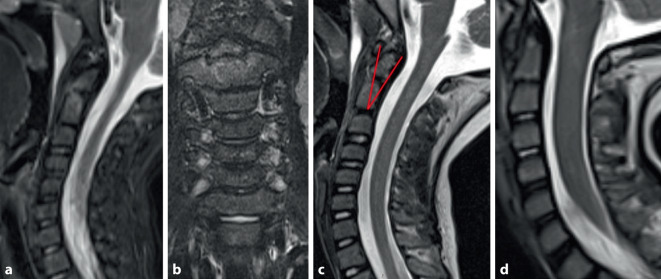

Epiphysiolysis of the dens axis is a rare injury in childhood but should be reliably investigated in the presence of typical pathological mechanisms. In our case, the injury in a four-year-old boy after a fall on his neck could not be diagnosed in the initial X‑ray. The diagnosis was made by means of an MRI scan performed during the course of the case and conservative treatment with a cervical collar was provided. The 10-year follow-up showed mild impairments, especially when remaining in a flexed position for long periods (e.g. when reading). In addition, the question arises retrospectively as to whether an additional injury to the C2/3 led to spontaneous fusion of the segment.